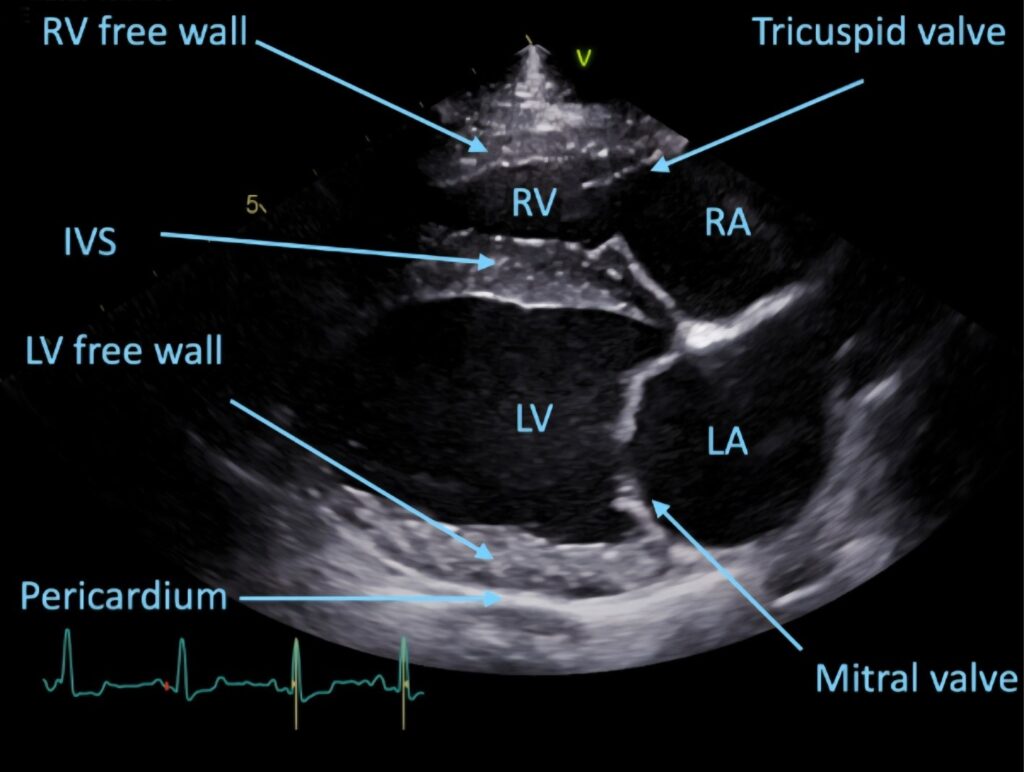

• 판막질환(MVI, TVI, AS, PS 등)